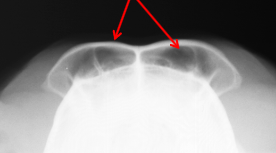

ID Radiographic View

Frontal Sinus View

ID

Frontal Sinus

Ethmoid Turbinates

Maxillary Turbinates

Nasopharynx

Maxillary Recess